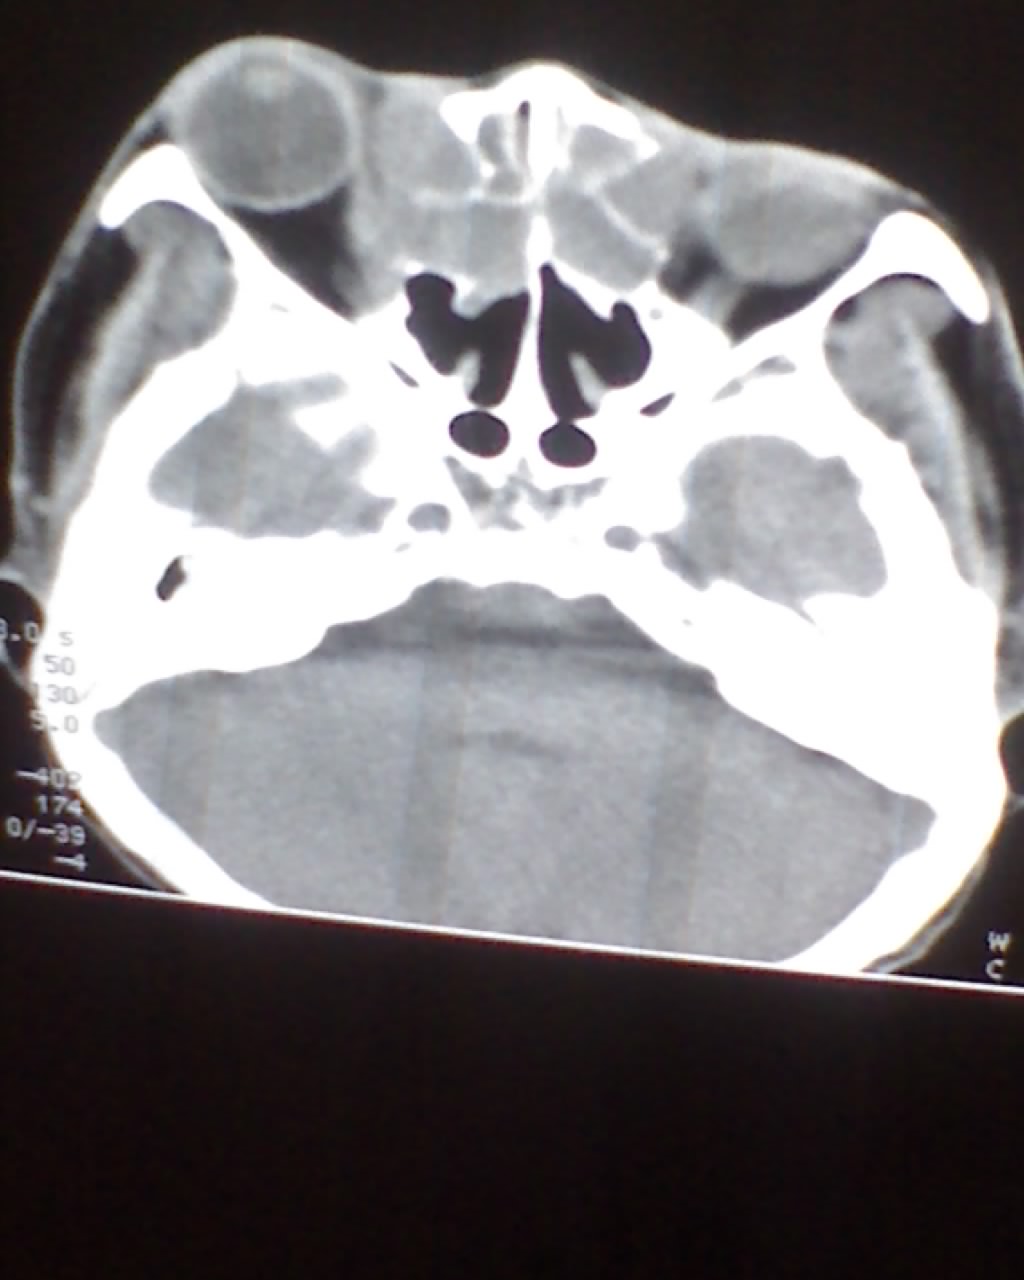

女,45岁,右眼突出,视力模糊来诊。

1)不排除嗅神经母细胞瘤侵犯双侧眼眶可能。2)双侧额窦及双侧蝶窦炎症。

考虑筛窦粘液囊肿。双筛窦、额窦、蝶窦炎症。

双侧额窦,筛窦可见软组织影充填,筛板破坏,肿块突向双侧眼眶内,以右侧为明显,右侧眼球向前外推压,右视神经稍外移。

考虑良性病变,黏液囊肿可能性大,不除外内翻乳头状瘤等,建议强化.前者不增强.